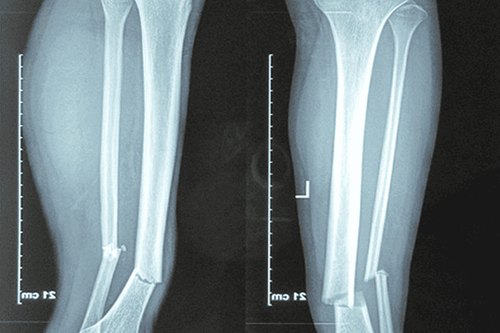

Em bị té xe, sau khi té thì em bị gãy hai ống xương bể nhiều mảnh, 1/3 phần chân dưới gần cổ chân và mất miếng xương 3cm tròn. Vậy bác sĩ cho em hỏi gãy hai ống xương kèm mất xương có sao không? Việc này có ảnh hưởng về sau không? Xương có hồi phục và liền lại chỗ mất không thưa bác sĩ? Em cảm ơn.